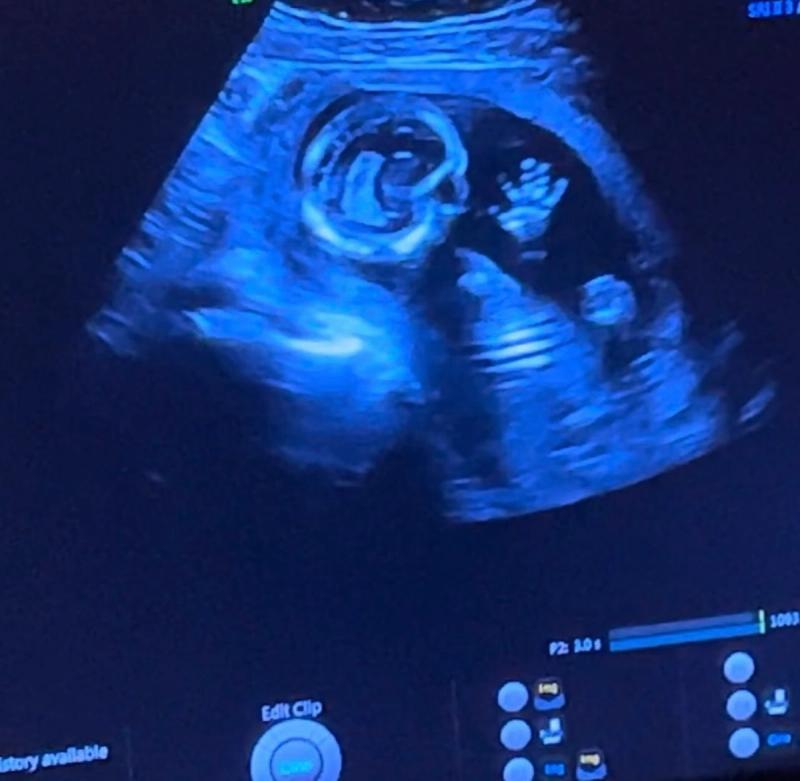

Aan het einde van de week hadden we de eerste afspraak bij de verloskundige. We zagen een kloppend hartje en ik was verder in de zwangerschap dan we aanvankelijk dachten. De uitgerekende datum was 30 augustus, Oscars verjaardag. De misselijkheid bleef, en in de weken die volgden, bleef ook de spanning. Ik liet iedere week een pretecho maken om zeker te weten dat het hartje nog klopte.